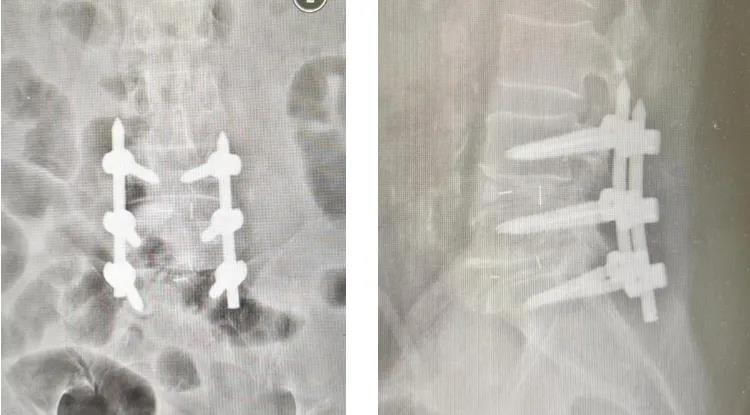

腰腿痛不是一种病,而是腰椎及周围组织病变引发的症状,核心根源多为神经受压。我们的腰椎椎管内布满神经根和马尾神经,它们像“电线”一样连接大脑与下肢,负责传递感觉和运动信号。腰椎管狭窄,韧带肥厚、骨赘增生导致椎管变窄,压迫马尾神经;同时由于患者过度肥胖,皮肤软组织较厚,传统开放手术创伤大,出血多,脊柱微创团队决定行OSE内镜辅助下L4/5、L5/S1减压融合内固定术。于12月23日,由临床经验丰富的唐福兴博士为患者进行手术主刀。借助OSE内镜系统的高清视野,唐福兴博士在脊柱内镜下精准地为患者解除椎管狭窄,释放受压的神经根,并在C臂透视下精准经皮植入椎弓根螺钉重建脊柱稳定性。脊柱内镜技术的核心原理,就像医生带着“高清显微镜”和“精细工具”,通过微小切口进入脊柱,精准清除病变组织、解除神经压迫——它无需大面积剥离肌肉,也不用过多破坏腰椎骨性结构,全程在可视化视野下操作,实现“微创+精准”双重目标。